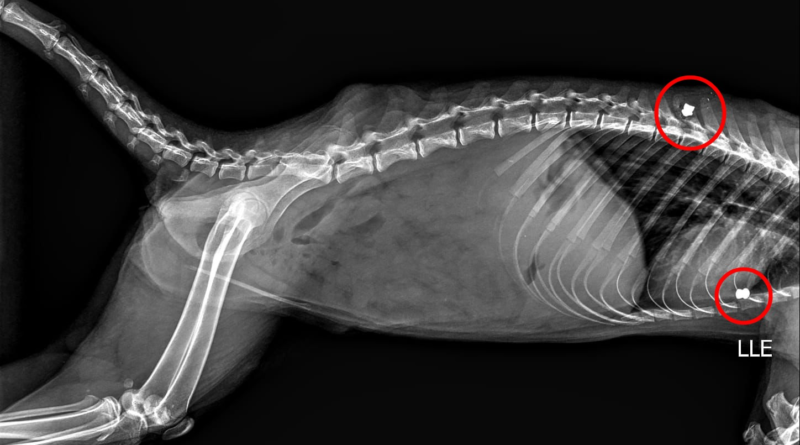

O animal foi socorrido em 15 de abril pela Secretaria do Meio Ambiente e segue em atendimento veterinário especializado. Segundo a prefeitura, um raio-X mostrou dois chumbinhos alojados no corpo do quati.

Raio-X de quati baleado com chumbinho e resgatado em bosque de Marília

Prefeitura Municipal de Marília/Reprodução